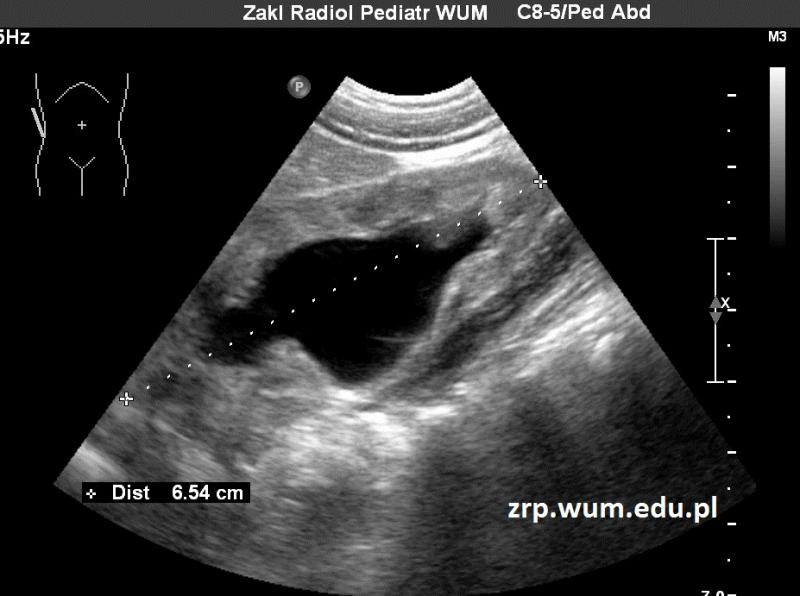

Przypadek 55: 16-letni chłopiec z podejrzeniem guza śródpiersia górnego, wykrytego w kontrolnym badaniu echokardiograficznym.

Rozpoznanie: Na zdjęciu RTG klatki piersiowej stwierdzono poszerzenie cienia śródpiersia po stronie lewej, w rzucie lewej wnęki. W trakcie dalszej diagnostyki rozpoznano chłoniaka.